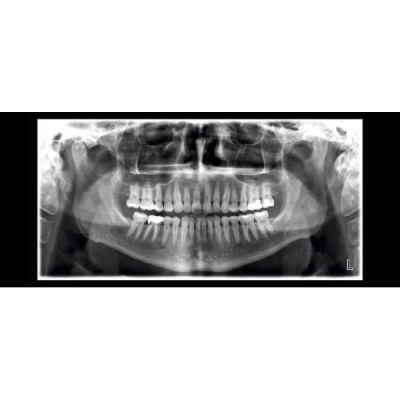

Planmeca ProMax SCARA2 Ceph рентгенологическая установка принципиально новой конструкции, обеспечивающая широкий диапазон возможностей получения внеротовых рентгеновских изображений.

- Стандартная панорама взрослого

- Стандартная панорама ребенка

- Фокальное пятно 0,5 мм, анодное напряжение 54-84 кВ, анодный ток 1-16 мА, время экспозиции для панорамных снимков от 2,5 до 16 сек, время экспозиции для цефалометрических снимков от 0,2 до 19 сек, увеличение панорамной экспозиции 1,2, увеличение цефалометрической экспозиции 1,08-1.13.

- Технические характеристики цифрового сенсорного датчика Dimax4: поле изображения Pan/Ceph 14х30/27х30 см, активная область Pan/Ceph 9х136/9х270 мм, число пикселей Pan/Ceph 1435х2943/2174x1930, размер пикселя датчика 48х48 мкм, разрешение Pan/Ceph 9/5,0-3,8 пар линий/мм, интерфейс Ethernet.